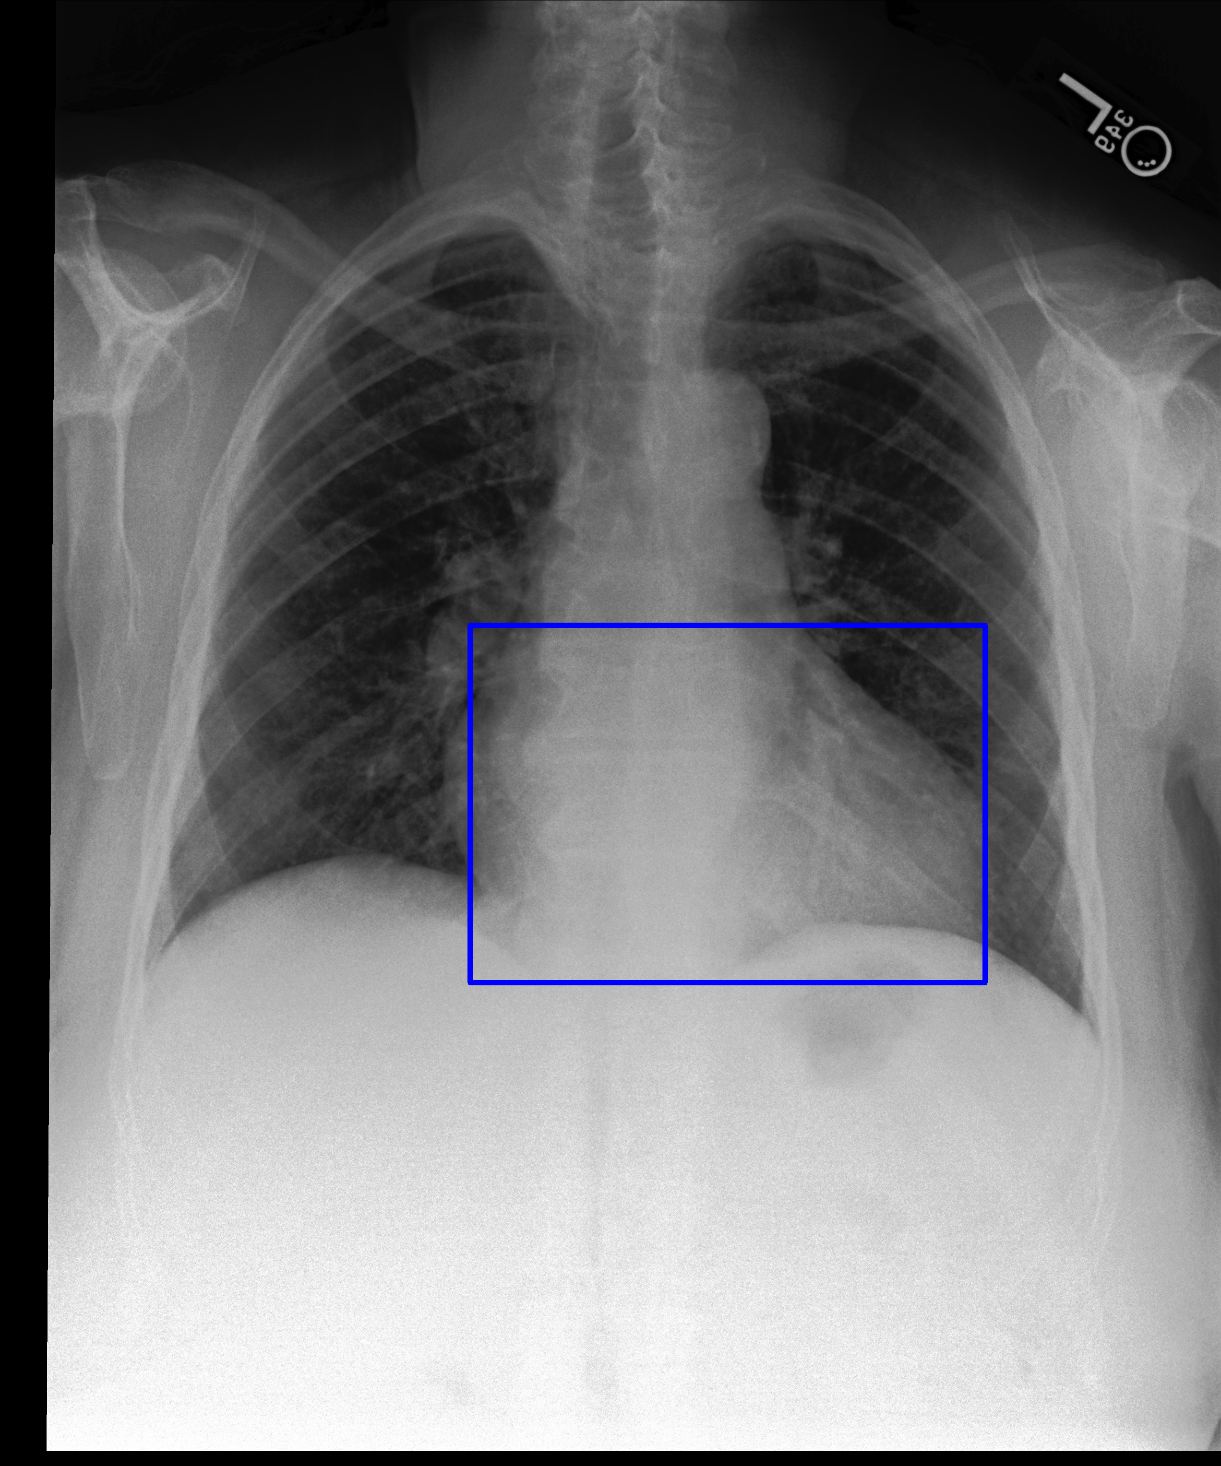

Image 1 CS RCA

[Uncaptioned image] [Uncaptioned image] [Uncaptioned image]

Ground Truth No findings No findings

CheXGCN L4 L1, L2

AnaXNet No findings No findings

Figure 2: Examples of the results obtained by our best two models. The overall chest X-ray image is shown alongside two anatomical regions. The predictions from best performing models are compared against the ground-truth labels.